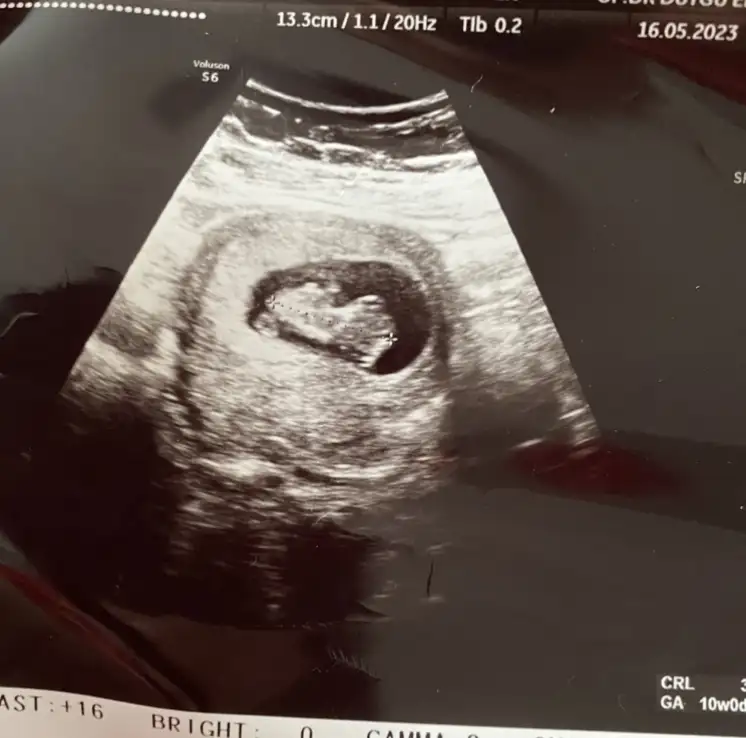

Seninki belli baya benimkine dün baktım arkası dönüktü bizeEki Görüntüle 3248976 10 haftalık olmuşuznub teorisinden anlayan var mı? Cinsiyet tahmini yapabilecek misiniz?